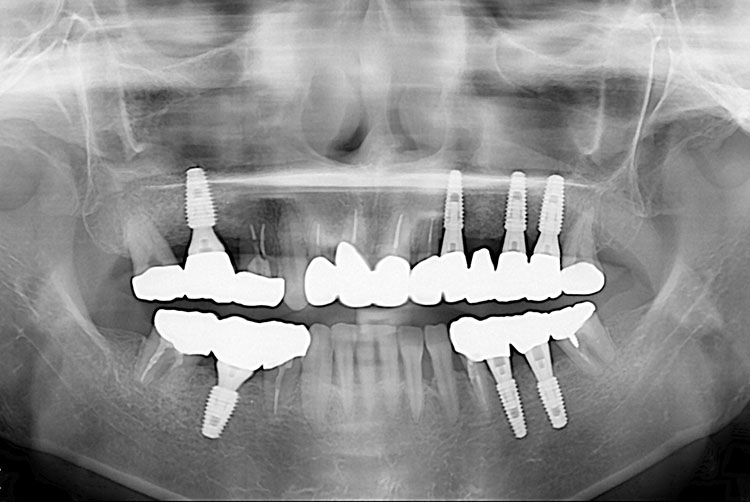

[임플란트] 임플란트

치료전 : 2016-07-09

세종치과는 많은 환자와 다양한 케이스를 바탕으로 항상 편안한 임플란트 수술을 제공하고자 노력하고,

오래동안 튼튼히 쓸 수 있는 임플란트 수술을 가장 큰 목표로 삼고 있습니다